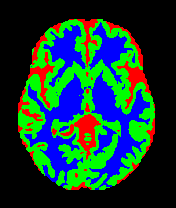

• OASIS-1 [34]: Derived from the Open Access Series of Imaging Studies, this dataset comprises T1-weighted MRI scans from 421 subjects (aged 18–96). The images were acquired with a resolution of 176×208176\times 208 pixels and a slice thickness of 1.25 mm (TR=9.79.7 ms, TE=4.04.0 ms, TI=2020 ms). Following standard protocols, we utilize the provided manual segmentation masks for Cerebrospinal Fluid (CSF), Grey Matter (GM), and White Matter (WM).

• MRBrainS13 [35]: From the MICCAI 2013 challenge, this dataset contains multi-sequence scans of 20 subjects acquired on a 3.0T Philips Achieva scanner. It provides T1 (TR: 7.97.9 ms, TE: 4.54.5 ms), T1-IR, and T2-FLAIR sequences. All scans are co-registered and bias-corrected with a voxel spacing of 0.96×0.96×3.000.96\times 0.96\times 3.00 mm. We utilize the provided labels for CSF, GM, and WM segmentation.

7 Qualitative Evaluation

Fig. 8 and Fig. 10 provide qualitative comparisons on the OASIS-1 and MRBrainS13 datasets, respectively. It is visually evident that the baseline predictions (c) and standard augmentations (e.g., (d), (g), (i)) frequently suffer from noisy artifacts, blurred boundaries, and mis-segmentation of intricate anatomical structures. In stark contrast, our ”Ours+” enhanced methods (e.g., (e), (h), (k)) consistently produce segmentation maps that are visibly cleaner, more spatially coherent, and demonstrate significantly sharper adherence to the Ground Truth (b). This superior fidelity is particularly noticeable in the complex sulcal patterns and holds true across all three backbones (rows), confirming that our framework yields more robust and anatomically plausible results.